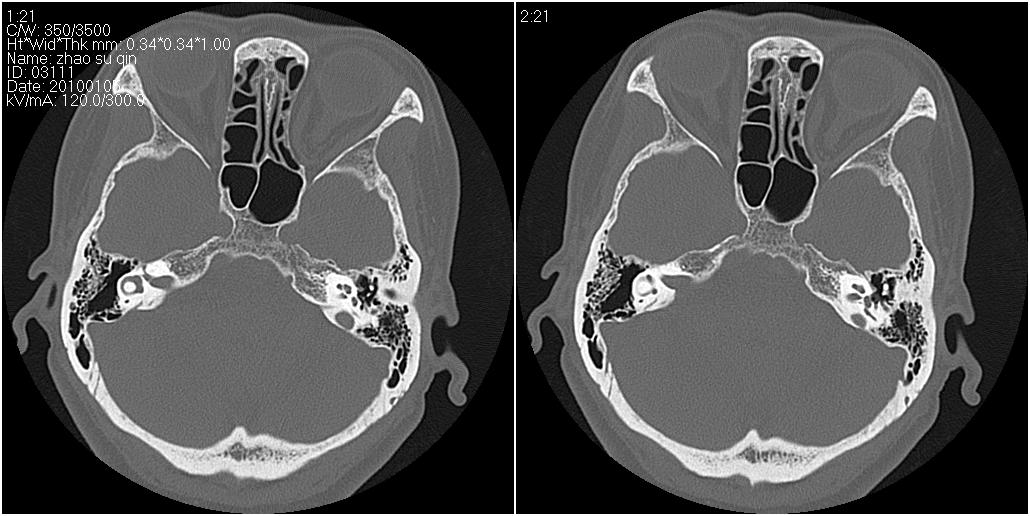

标题: CT24015:一个头部外伤患者进行鉴定,除了左侧筛板骨折,哪 [打印本页]

标题: CT24015:一个头部外伤患者进行鉴定,除了左侧筛板骨折,哪

左眶下裂部好像有骨折 似有小碎骨片

1)左侧筛板骨折。2)双侧筛窦炎症(或积血)。